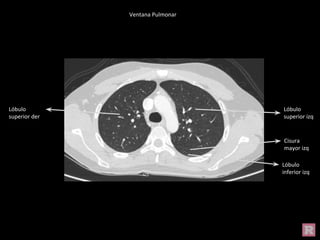

Ventana Pulmonar

Lóbulo superior

izq

Lóbulo superior der

Lóbulo inferior izq

Lóbulo superior der Lóbulo superior

Cisura mayor izq

Lóbulo inferior der

Cisura Mayor der